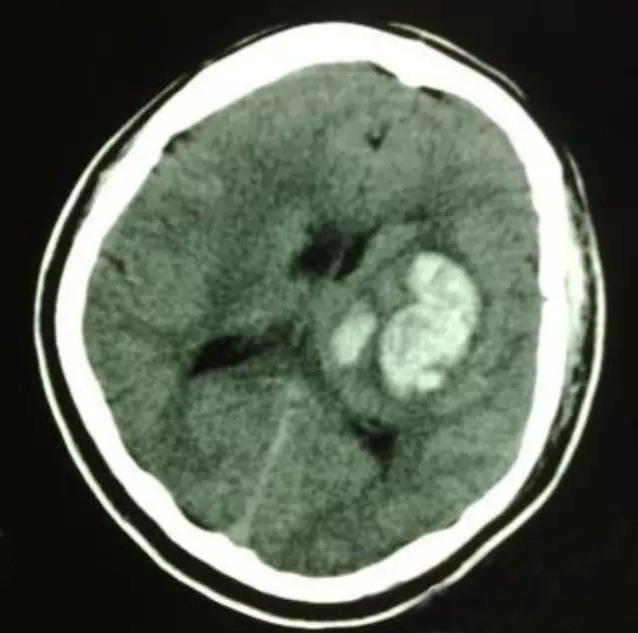

高血压脑出血

高血压脑出血后血肿周围水肿相关影响因素的研究进展

隐形杀手在身边:警惕高血压脑出血的致命威胁

高血压脑出血手术治疗研究进展

非对比剂CT影像组学和机器学习在高血压脑出血诊疗过程中应用研究进展